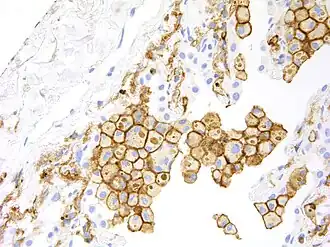

Immunohistochemical analysis of HAVCR2 in paraffin-embedded human lung carcinoma tissue.

HAVCR2 expression is up regulated in tumor-infiltrating lymphocytes in lung,[8] gastric,[30] head and neck cancer,[31] schwannoma,[32] melanoma[33] and follicular B-cell non-Hodgkin lymphoma.[34] It is also up-regulated in tumour-associated macrophages in various malignancies, including melanoma, especially in immunotherapy-resistant context.[9]